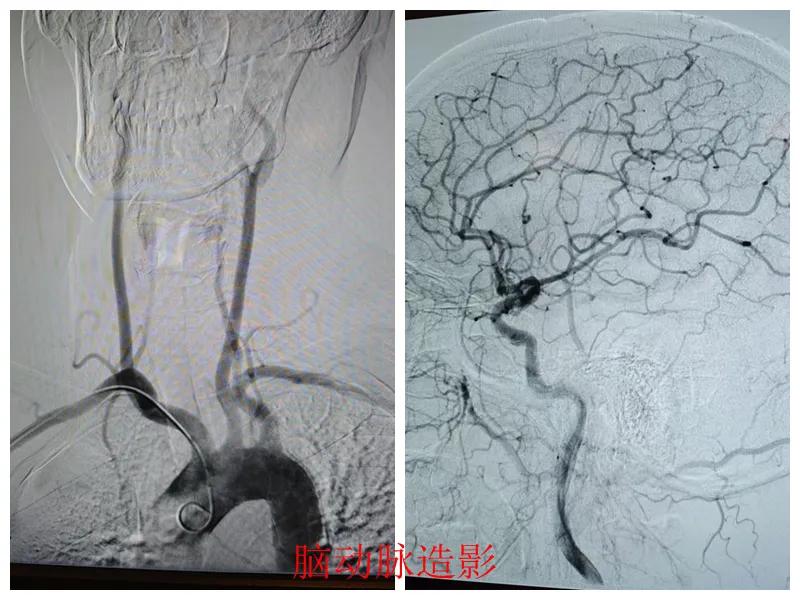

術前準備完善后,在王瑾院長帶領下,心血管內科主任李慧新、影像科主任宋貴良、副主任醫(yī)師趙進科等緊密協(xié)作,成功為患者實施了冠狀動脈造影及腦動脈造影兩項檢查。冠狀動脈造影結果提示:患者右冠狀動脈慢性閉塞,腦動脈造影提示腦血管多支狹窄病變。